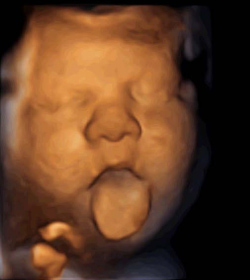

Si te haces una ecografía en 4D (entre la semana 24 y 30 de embarazo es el mejor momento) o una ecografía 5D es muy probable que la imagen que veas en la pantalla del ecógrafo sea muy similar a la de un bebé recién nacido. Sobre todo, si te la haces avanzado el tercer trimestre, cuando ya está más regordete. Sin embargo, para los médicos hasta que tu hijo no nazca, le van a seguir considerando un feto. Así que, no te extrañe que en los informes médicos aparezca la frase “feto de 36 semanas".